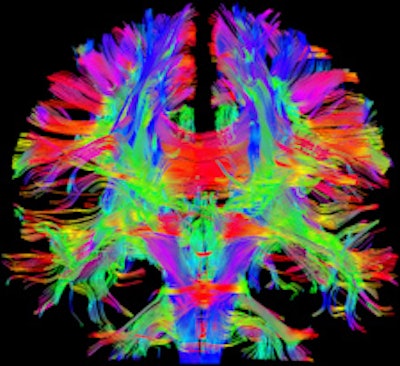

Siemens Healthcare is introducing a 3-tesla machine and is emphasizing its value as a research tool in neurology, physiology, and tissue metabolism studies. The company believes that the Magnetom Prisma sets new standards, having a gradient strength of 80 mtesla/m combined with a slew rate of 200 tesla/m/sec.

The system also offers a tandem configuration unavailable in any other commercial whole-body system, according to the vendor. The device's combination of high gradient strength and fast gradient switching speed allows for increased image quality compared with conventional devices. Due to this combination of high spatial and temporal resolution, the new machine can reportedly achieve good image quality, especially in very demanding applications. Furthermore, by combining high gradient strength with fast gradient switching speed, the Magnetom Prisma offers new possibilities in areas such as diffusion imaging, because even minor diffusion effects can be captured. Moreover, the diffusion spectrum imaging (DSI) application makes it possible to resolve fine anatomical details of the brain, such as crossing white-matter fibers by using up to 514 diffusion encoding directions, Siemens stated.